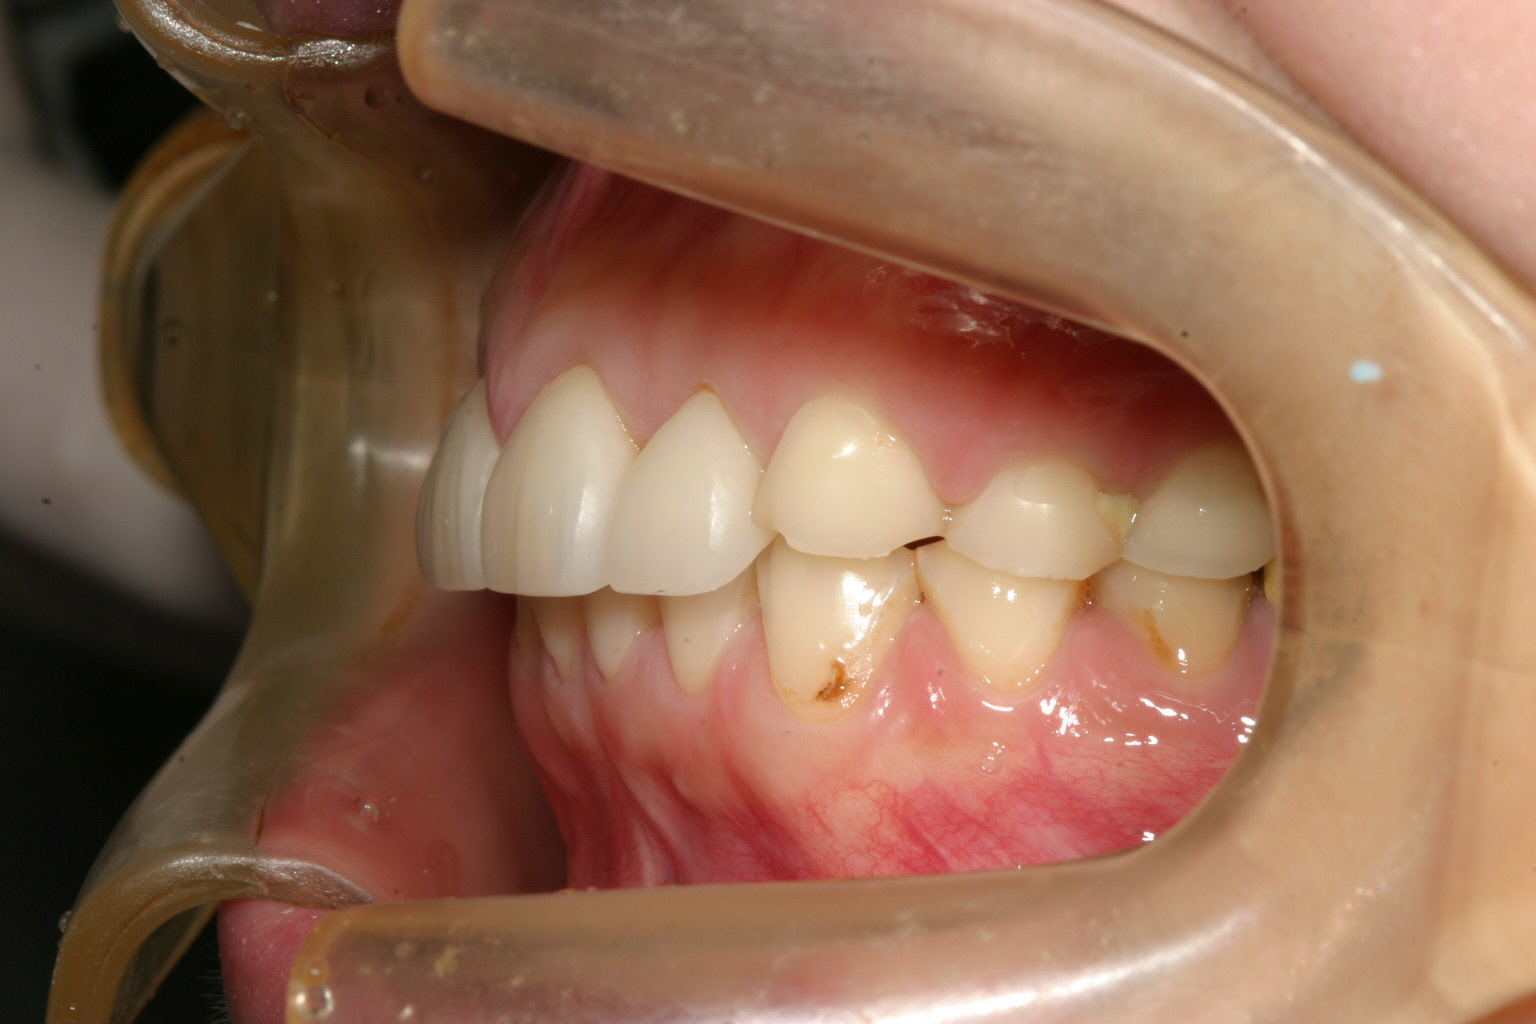

横からのかみ合わせですが奥歯が摩耗して低いとこの様に下顎が後ろに下がり顎関節症が生じ出っ歯感になります。